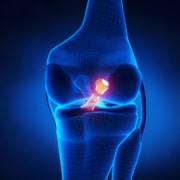

This question is actually quite complicated to answer for orthopedic surgeons. Everyone’s anatomy is unique and built differently. In the past, surgeons used to say after joint replacement surgery, that a patient’s artificial joints would last about 10 to 15 years. However, with modern materials and updated surgical techniques, current studies and evidence-based research show that approximately 96 percent of today’s modern joint replacements, especially knee replacements, will still be functioning past the 15-year mark.

Your joint replacement does not necessarily have a warranty, per se, as each patient is unique in both their anatomy and their level of physical activity. Sometimes a patient is notified by their surgeon that they will require revision surgery. This means that the patient will need to undergo a second surgery to fix their problem. The failure of a joint replacement can occur for variety of different reasons. These include infection, trauma, loosening of the implant, degeneration (wearing out), or poor positioning of the original implant.

With a drastic improvement in surgical techniques, high-quality care and materials, such as metal, ceramic, and plastic, the new artificial joint is attached the bone, allowing the bone to grow into the implant. Physical therapy will be recommended afterwards by your surgeon, as rehabilitation will dramatically increase mobility, help with balance, and decrease the recovery time, giving the patient a higher quality of life in the end.